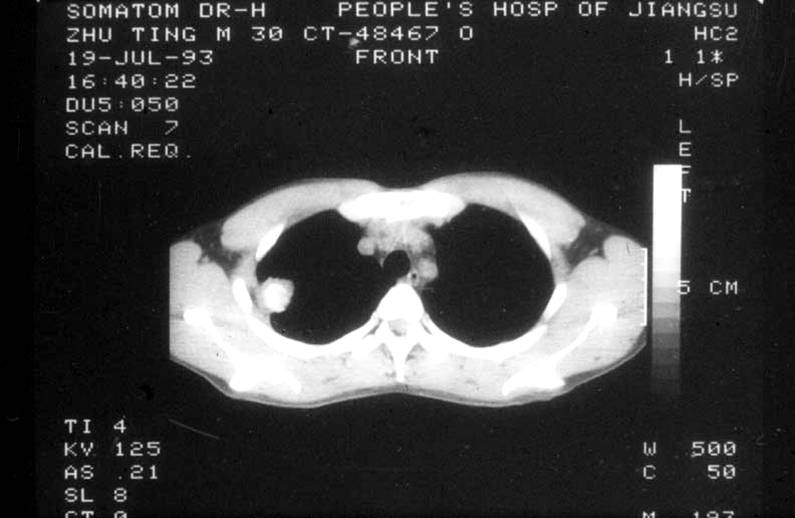

胸骨柄平面(图)

胸骨柄平面